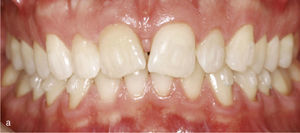

El paciente se presentó en nuestro centro con el siguiente cuadro: dentición permanente con proinclinación de dientes anteriores y desviación de la línea media, diente 53 persistente, dientes 13 y 23 elevados y desplazados hacia vestibular, curva de Spee marcada con extrusión del sector anteroinferior, dientes rotados y apiñados en maxilar y mandíbula, clase II de Angle con un resalte de 4mm y sobremordida de 0mm, además de ausencia de guía canina (figs. 13a a 13c y 14a a 14e).

El plan de tratamiento incluyó el establecimiento de una clase I de Angle con sobremordida horizontal y vertical fisiológicas mediante la distalización del sector posterosuperior, con corrección de los caninos superiores y aseguramiento de una guía canina. Las arcadas se dotaron además de una apariencia armoniosa eliminando la giroversión y los apiñamientos mediante la reducción del esmalte interproximal y el ajuste de las líneas medias. El paciente optó por un tratamiento con el sistema Invisalign alternativo a la aparatología fija con brackets. Se colocó un atache rectangular vertical en los dientes 13 y 23 y, en el curso del tratamiento, también en los dientes anterosuperiores y en el diente 43. Además durante todo el tratamiento el paciente llevó elásticos de clase II en ambos lados, del diente 14 al diente 46 y del diente 24 al diente 36 para obtener el anclaje necesario durante la distalización. La figura 15 muestra la situación intraoral de un caso similar con brackets en los dientes 13 y 46. En la zona de los brackets se acortó el alineador. Además de los alineadores se utilizaron elásticos de clase II del diente 13 al diente 46.